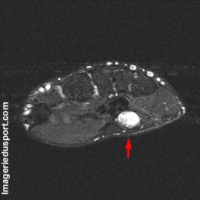

Le syndrome du marteau hypothénar est une cause possible d’ischémie digitale, classiquement unilatéral. Il touche la main dominante lorsqu’elle est utilisée comme un marteau : certains travaux manuels (carreleurs, mécaniciens) ou sports (handball, golf). Il est la conséquence de traumatismes répétés de l’artère ulnaire dans l. Il existe groupes : Eminence Thénar, Hypothénar , muscles interosseux et lombricaux.